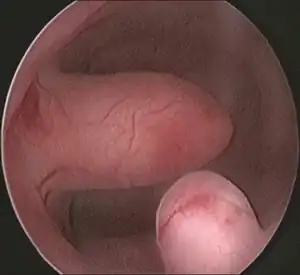

| Endometrial polyp at hysteroscopy | |

Hysteroscopy

Other tests include hysteroscopy.[2]

Pedunculated endometrial polyp -

Sessile endometrial polyp -

Bleeding and endometrial polyp -

Multiple endometrial polyps -

Multiple endometrial polyp